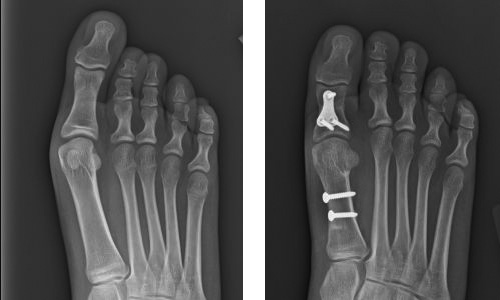

We had an almost identical case in our residency program (Attending: Michael Theodoulou, DPM). Fourteen year-old identical twin sisters presented with bilateral elongation of the 1st metatarsal and proximal phalanx. We performed a cylindrical wedge osteotomy of the proximal phalanx measuring approximately 8mm, and a sagittal Z shortening osteotomy of the 1st metatarsal with removal of 10mm.

Pre- and Post-op X-Rays

The phalanx was fixated with a locking T plate, while the metatarsal osteotomy was fixated with two 2.7 compression screws. Patients are s/p 13 months on the right and 16 months on the left. Both patients are doing exceedingly well.